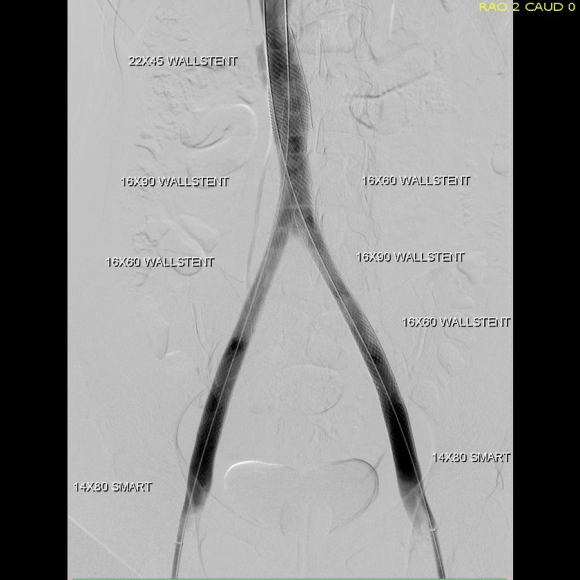

And it is with this wisdom that I see the increasing numbers of chronic venous occlusions. For example, the patient whose venogram is pictured above initially complained to her obstetrician of persistent heaviness in the pelvis and swelling of the legs after delivering a healthy baby. MRV showed abundant pelvic collateral veins and she was referred to me.

She had iliocaval occlusion, chronic. Her symptoms were over two years, and were ever worsening. She hadn’t developed permanent skin changes of chronic venous insufficiency, but probably would in a decade or sooner. I recommended venography and an attempt at recanalization.

The procedure went well, and her symptoms abated. For my trainees, the absence of collaterals in the after image is the sign that hemodynamically, the revascularization is the preferred route of egress. Surprisingly, this has stayed open over two years, but again, my exceedingly well paid sewer gentleman consultant, had something to say about it.